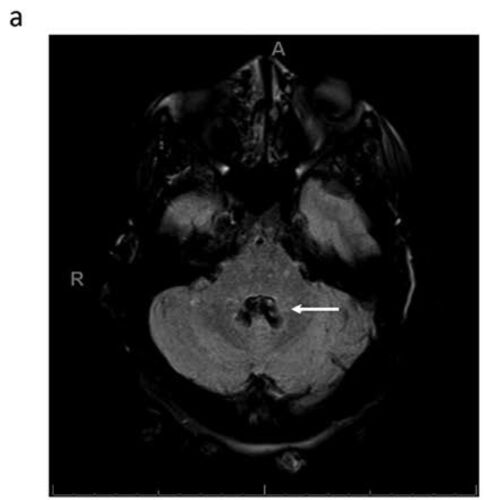

症例118:視線が上下してしまい視線が合わせづらいと訴える23歳女性(Am J Emerg Med. 2021 Jan;39:259.e1-259.e3.)

病歴/身体所見 ・23歳女性 ・既往歴なし ・2日間にわたり視線が維持できず、眼が上下するようで視点が合わせづらいと訴えER受診 ・これに先立って両側性拍動性頭痛があり、安静により改善したが視覚の異常が持続していたという ・頭部外傷/視力低下/眼痛/運…